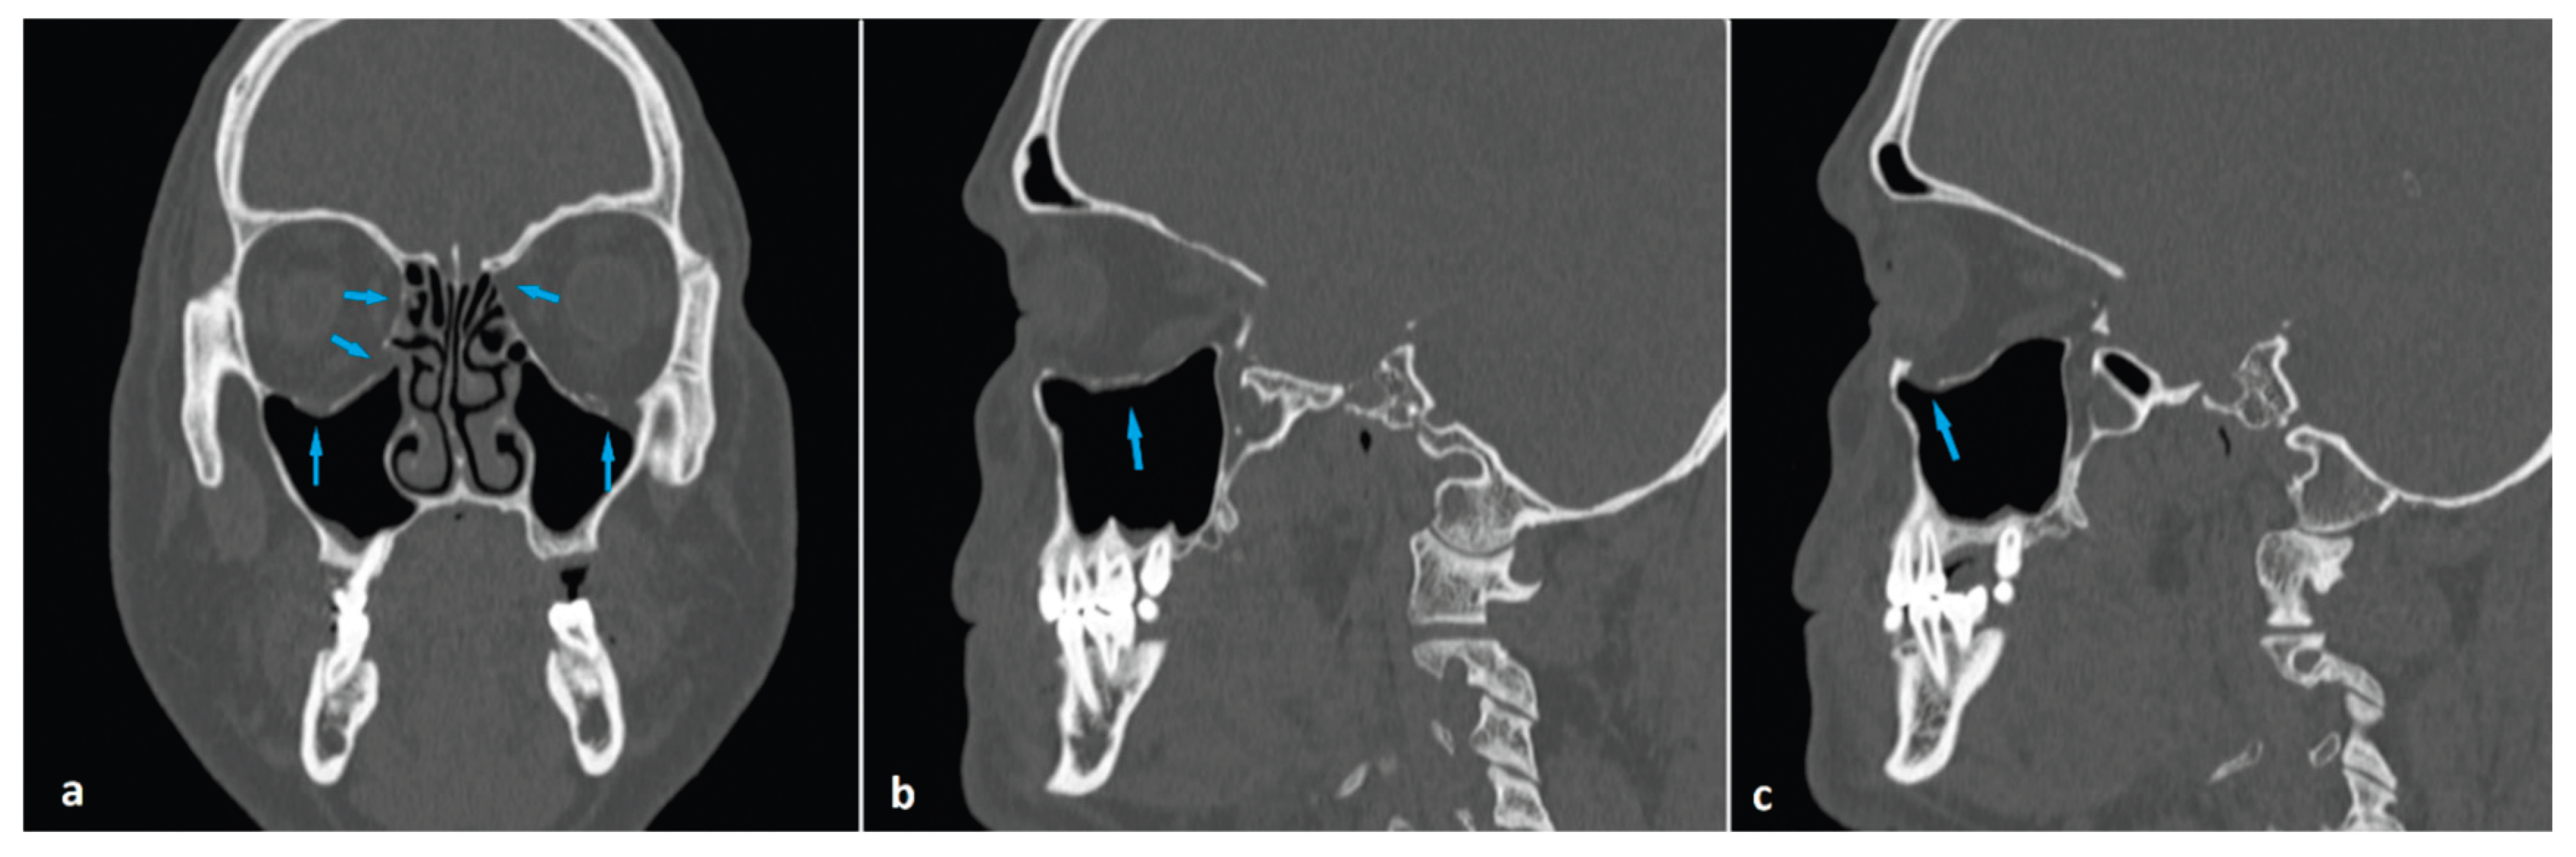

Figure 5. Coronal (a) and sagittal (b and c) maxillofacial computed tomography images of a 57-year-old man presenting with head trauma. He had bilateral blowout fractures (arrows) of the medial orbital walls and orbital floors (a). Right and left orbital floor fractures with herniation of fatty tissue into the maxillary sinuses (arrows) are shown in b and c, respectively.

There are reports in the literature indicating that OBF, although rare, can occur bilaterally. Bilateral OBF has been reported to occur most commonly in older adults and as a result of exposure to high-energy trauma. The medial orbital wall has been shown to be more frequently affected in bilateral cases [15,18,19]. In our sample, there were two (1.8%) subjects with bilateral OBF. Both were male and above the median age of the case population. One had fractures in the medial walls, and the other had fractures in both the medial walls and the orbital floors (Figure 5).